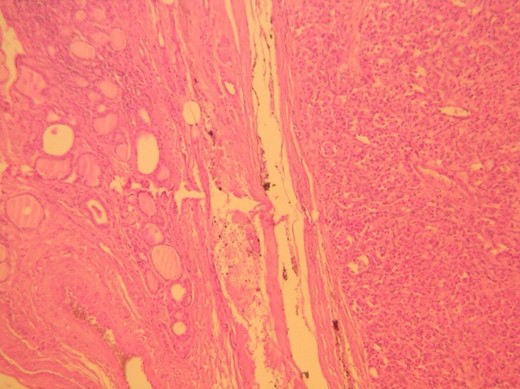

Histologic examination showed a 34 × 26 mm tumor on the left lobe which consisted of neoplastic cells nests arranged in a characteristic ‘zellballen’ pattern (Figs 1 and 2). Immunohistochemistry was positive for neuroendocrine markers (Chromogranin A, Synaptophysin, CD56, NSE, CD 57) and negative for cytokeratins (AE1/AE3, 7, 8, 19), Calcitonin, CEA and Thyroglobulin (Figs 3–5).

H&E ×400, original magnification. The tumor shows the characteristic ‘zellballen’ pattern.